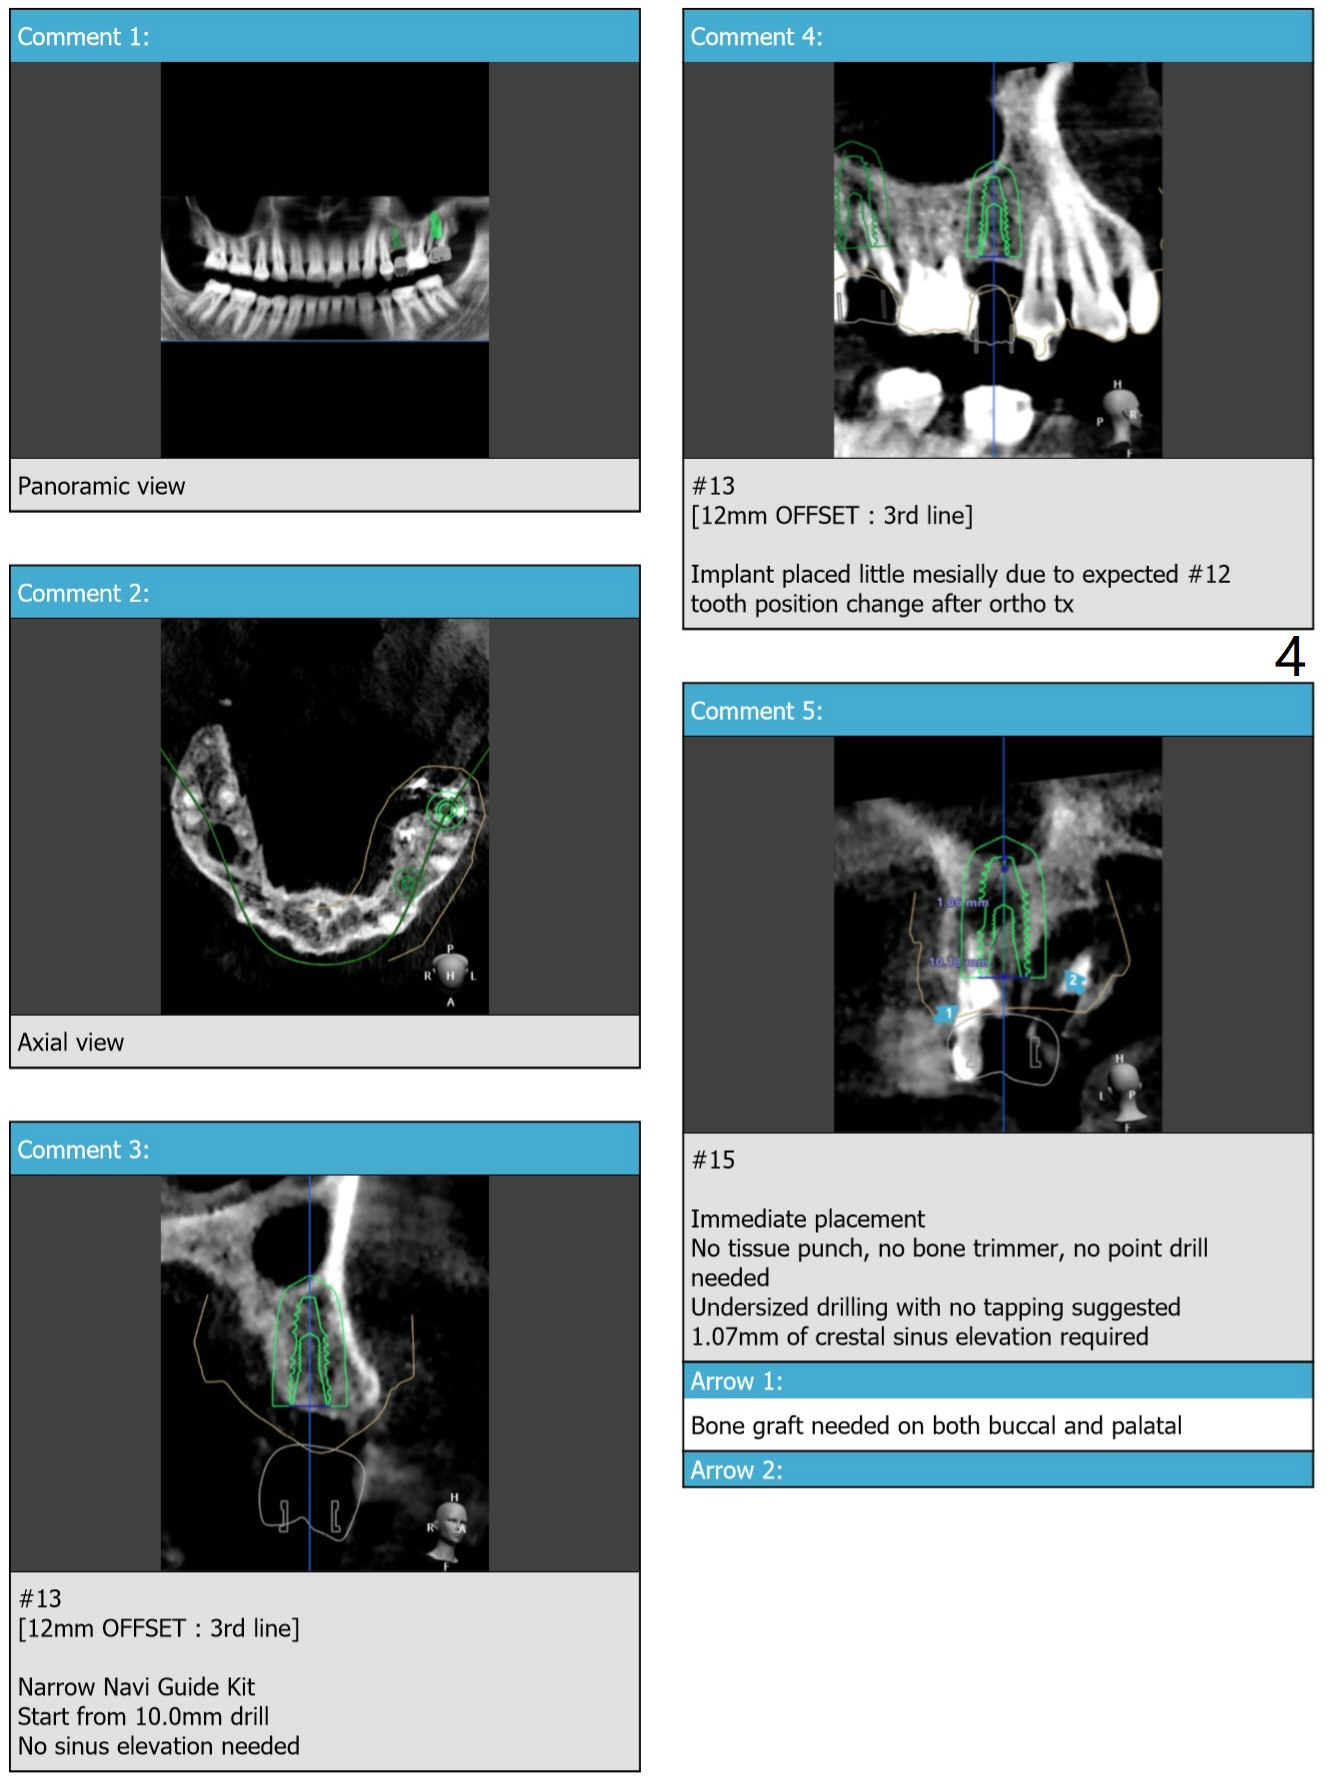

#13 Implant Mesial Placement

To close the diastema between #11 and 12 orthodontically, the implant at #13 will be placed slightly mesially.